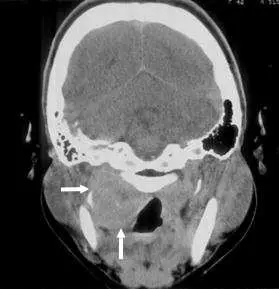

21 歲男性因上頸部硬塊求診,接受對比劑注射後的電腦斷層掃描如圖⽰,則最可能診斷為何?

圖示為頸部上段(upper neck)的對比劑增強軸位電腦斷層(axial contrast-enhanced CT)影像,白色箭頭指示兩處病灶:

- 右側(圖右側,箭頭指向):右頸深部淋巴結(jugular chain)明顯腫大,呈不均勻強化(heterogeneous enhancement),中央可見低密度區域,提示淋巴結中央壞死(central necrosis)——此為惡性腫瘤淋巴結轉移的典型表現,常見於 NPC 及鱗狀細胞癌(squamous cell carcinoma, SCC)轉移。

- 左側(下方箭頭指向):左側亦可見腫大淋巴結,同樣具有對比劑強化。

- 雙側頸部淋巴結腫大:NPC 具有高度淋巴轉移傾向,75-90% 的病例在影像上呈雙側頸部淋巴結擴散(bilateral neck spread),此為與其他頭頸癌不同的特徵。